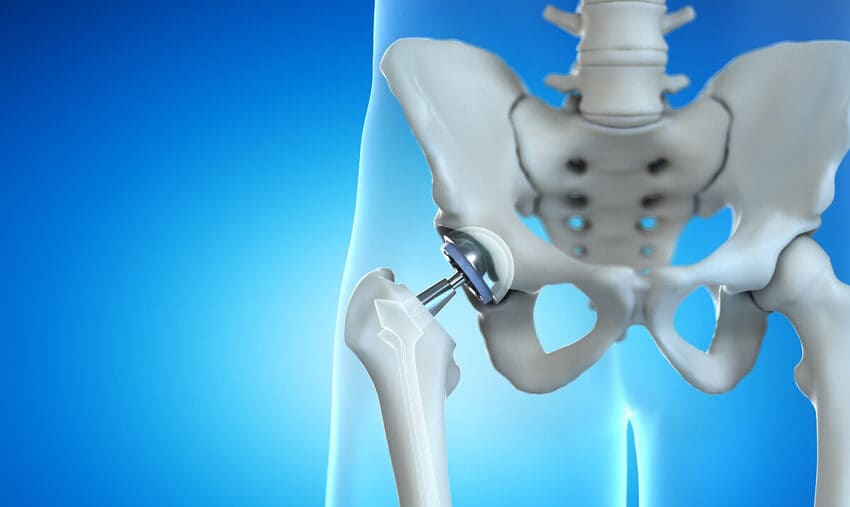

Total kalça protezi nedir?

Türkiye’de İstanbul’da total kalça protezi, kalça eklemindeki hastalıklı kıkırdak ve kemiğin cerrahi olarak yapay malzemelerle değiştirildiği cerrahi bir prosedürdür.

Kalça bir top ve soket eklemidir. Hastalık veya aşınma ve yıpranma nedeniyle hasar görebilir. Eklemin sadece bir kısmı hasar görmüşse, kısmi kalça protezi düşünülebilir.

Kısmi kalça protezi ameliyatında kalça yuvası genellikle sağlam bırakılır. Femur başı, total kalça protezinde kullanılana benzer bir yapay bileşenle değiştirilir. Bazen kemiğin üzerine bir cihaz yerleştirilir, böylece uyluk kemiğinin üst kısmının kesilmesi gerekmez. - Minimal invaziv kalça protezi